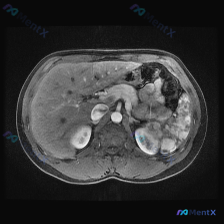

核心影像表现

- 脾脏:体积增大,内部可见多发明显的低信号结节影/斑片影,呈弥漫性分布,边界相对模糊

- 肝脏:肝实质信号欠均匀,可见多发斑点状、类圆形低信号影散在分布

- 右侧肾上腺区:可见类圆形高信号病灶,信号强度接近皮下脂肪

- 其他:胰腺、双侧肾脏、腹膜后大血管及肠道未见明确显著异常